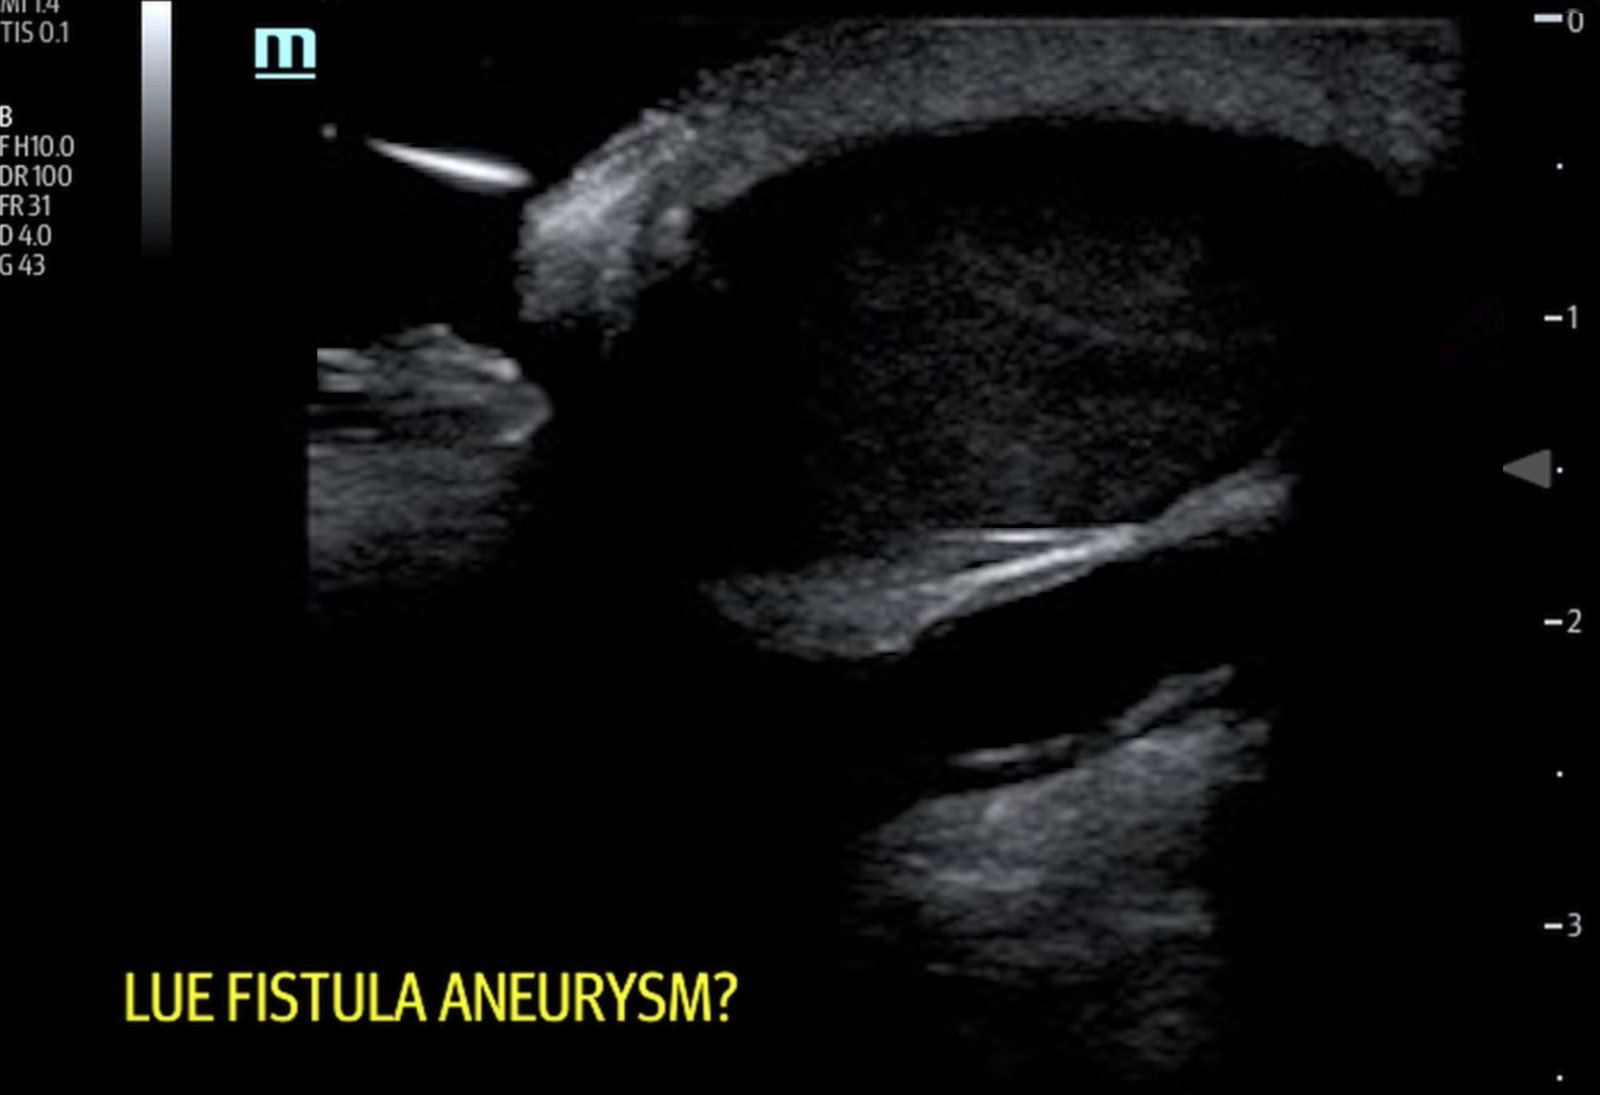

A bedside ultrasound of the mass demonstrated a large compressible hypoechoic structure (see purple outline) above the arteriovenous graft (see red outline). The contents demonstrated movement of fluid within the structure. This was confirmed with Doppler mode, which allowed for visualization of flow communicating between the structure and the underlying vessel, which is diagnostic for a pseudoaneurysm.

Pseudoaneurysms are a relatively rare complication of vascular access with an incidence of 2%-10%.3 They often result from weakening of the vessel wall secondary to inflammation from infection or chronic needling which leads to scarring.4 Concerning signs that warrant vascular surgery consultation include an aneurysm that is symptomatic, twice the size of the graft, expanding, threatened viability of overlying skin, or large/multiple aneurysms limiting number of cannulation sites.5 Doppler ultrasound is the principal means of diagnosis with a sensitivity of 94%.6 On ultrasound there are several characteristic findings that can alert the provider to the diagnosis of pseudoaneurysm. On color doppler, visualization of a communication between the vessel and fluid collection external to the vessel is diagnostic.7 This connection is classically described as the yin-yang sign.7 Spectral doppler can demonstrate biphasic flow through the communication.7